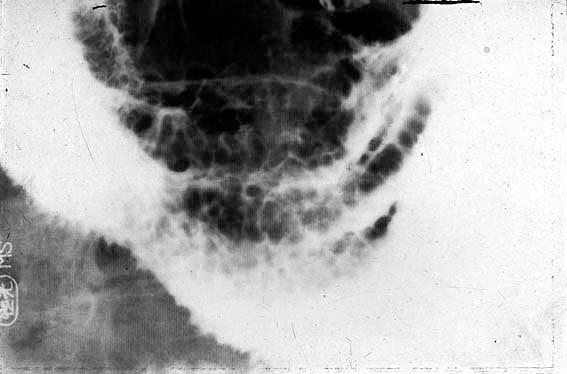

A case of Cronkhite-Canada syndrome with a protein losing gastroenteropathy.

Tumor-like lesions/Cronkhite-Canada syndorome

Location

Stomach/Antrum

Technique, Method

X-ray

Size

10 - 14